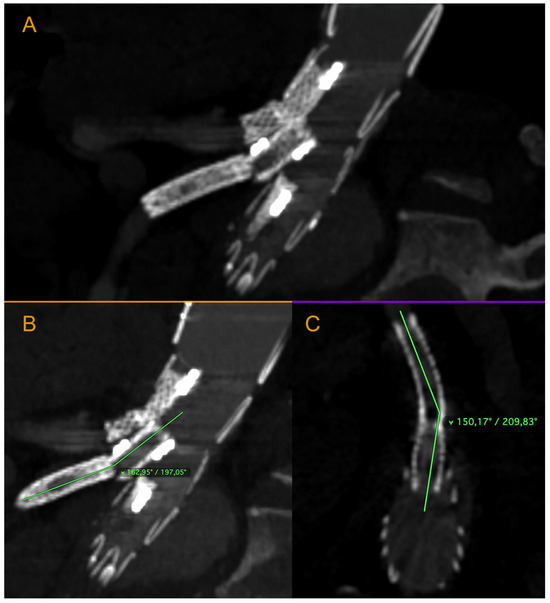

Figure 4. Ruptured superior mesenteric artery branch of stent-graft—the angle between the BeGraft and the vessel. The figure shows a divergence between the axis of the branch and the axis of the superior mesenteric artery. Panel (A)—sagittal projection, panel (B)—sagittal projection with marked angle, panel (C)—axial projection with marked angle. Pre-interventional Angio-CT scans, arterial phase.

As illustrated in Figure 4, the axis of the branch and the axis of the superior mesenteric artery have become misaligned. The forces exerted as a result of the endoleak may have created an angle and bending, potentially leading to dangerous stent material fracture and further leakage. This is an uncommon case, and it is difficult to find similar descriptions in the literature. It is important to highlight that the event we described occurred suddenly, prompting an urgent decision to implement the appropriate intervention. Throughout the observation period, the patient’s condition remained stable, and he experienced no pain. Endoleak treatment procedures were carried out as planned, and the aneurysm sac enlargement progressed slowly.